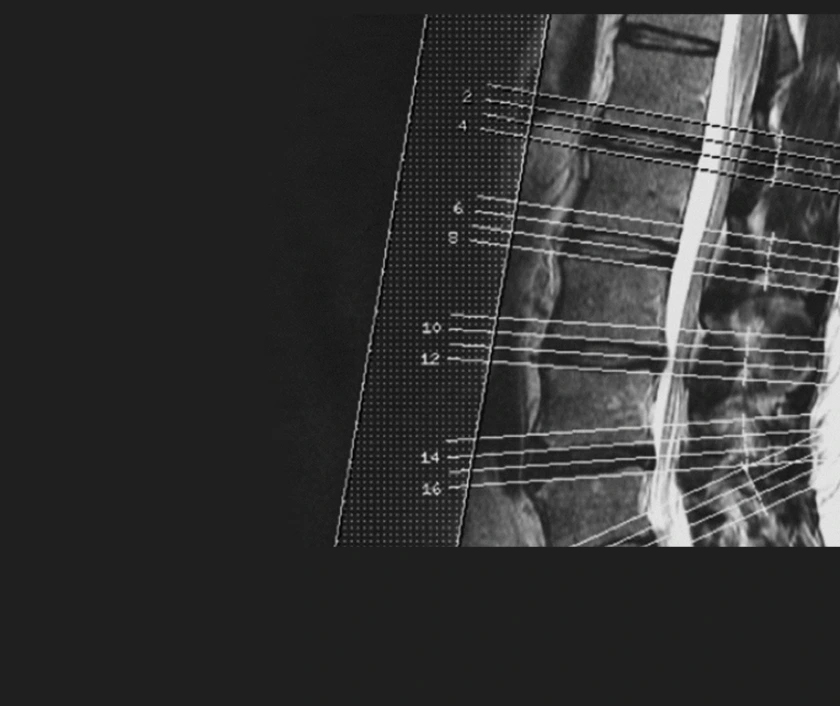

Slide the circle left or right to see how two scanners produce images of the same patient.

In the lower quality image, individual nerve roots and solid organ tissue are difficult to see

Imaging center protocols may prioritize speed over coverage.

When MRI sections are widely spaced, interpretation is more difficult, and radiologists can miss important information.

low resolution

high resolution

Widely spaced (~15 minutes)

Narrowly spaced (~40 minutes)